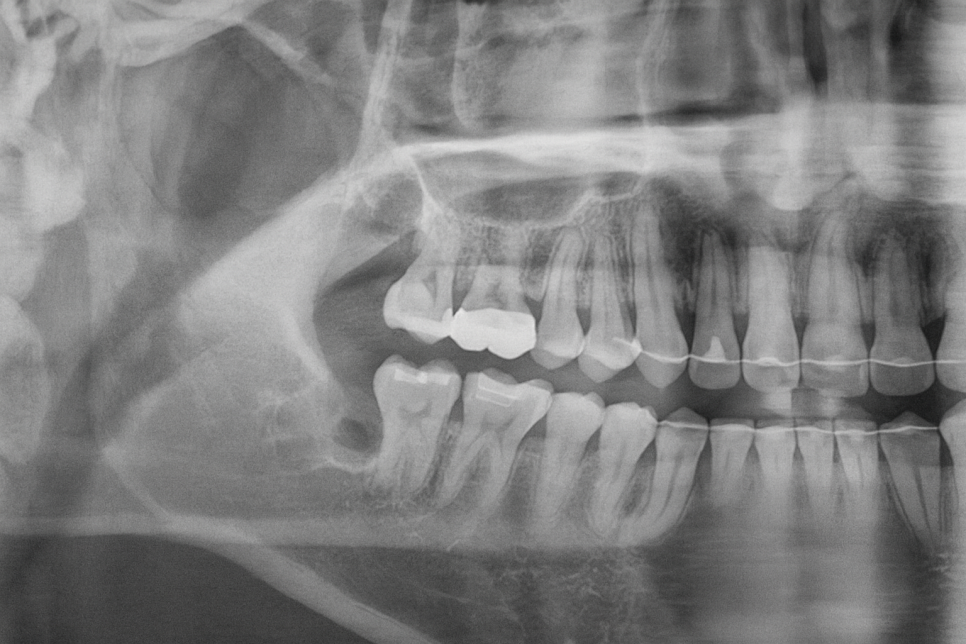

치아를 머리와 뿌리 두 갈래로 나눠줍니다.

이후 치아편을 꺼내주는데,

만약 분할을 했음에도 조각이 더 커서 꺼내기 힘들다면

분할한 머리 부분을 한 번 더 잘라낼 수도 있습니다.

제가 준비한 예시 사진처럼 여러 갈래로

절개하여 사랑니 발치를 진행한 경우,

혹여 치조골 속에 작은 조각이 남지 않았는지

주의 깊게 체크해야 된답니다.